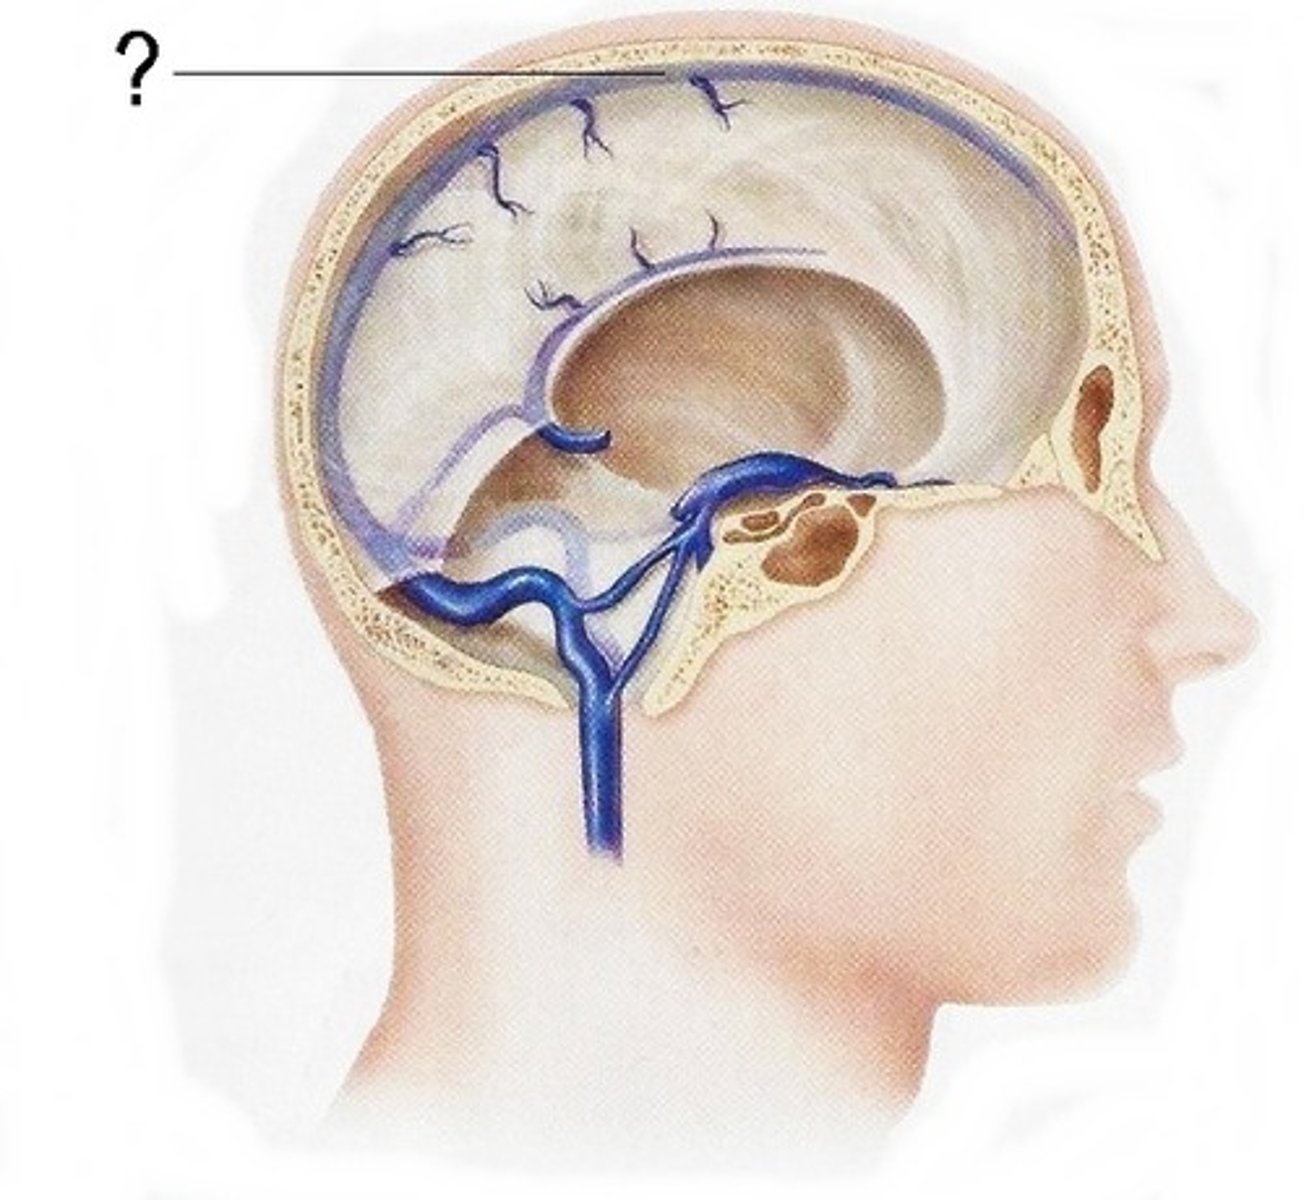

Dura mater

outermost layer of meninges - 2 layers, periosteal and meningeal

What is contained between the inner and outer layers of dura?

venous sinuses

what are the venous sinuses? where do they drain?

cerebrospinal fluid, they drain out of the internal jugular

superior sagittal sinus

inferior sagittal sinus